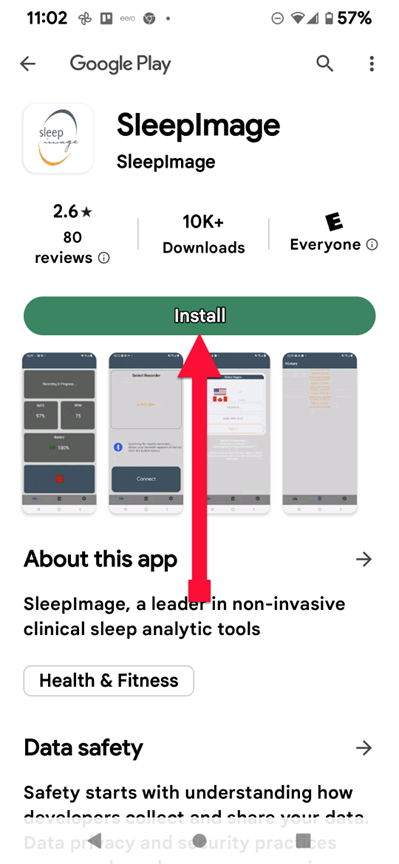

SLEEPIMAGE APP (Android)

SLEEPIMAGE APP (Android)

SLEEPIMAGE APP (Android)

SLEEPIMAGE APP (Android)

SLEEPIMAGE APP (Android)

SLEEPIMAGE APP (Android)

SLEEPIMAGE APP (Android)

SLEEPIMAGE APP (Android)

SLEEPIMAGE APP (Android)

SLEEPIMAGE APP (Android)

SLEEPIMAGE APP (Android)

SLEEPIMAGE APP (Android)

SLEEPIMAGE APP (Android)

SLEEPIMAGE APP (Android)

SLEEPIMAGE APP (Android)

SLEEPIMAGE APP (Android)

SLEEPIMAGE APP (Android)

SLEEPIMAGE APP (Android)

SLEEPIMAGE APP (Android)

SLEEPIMAGE APP (Android)

SLEEPIMAGE APP (iPhone)

SLEEPIMAGE APP (Android)

SLEEPIMAGE APP (Android)

SLEEPIMAGE APP (Android)

SLEEPIMAGE APP (Android)

SLEEPIMAGE APP (Android)

SLEEPIMAGE APP (Android)

SLEEPIMAGE APP (Android)

SLEEPIMAGE APP (Android)